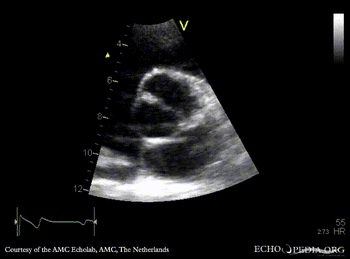

PSAX: double orifice of mitral valve Continuous-wave signal of mitral inflow